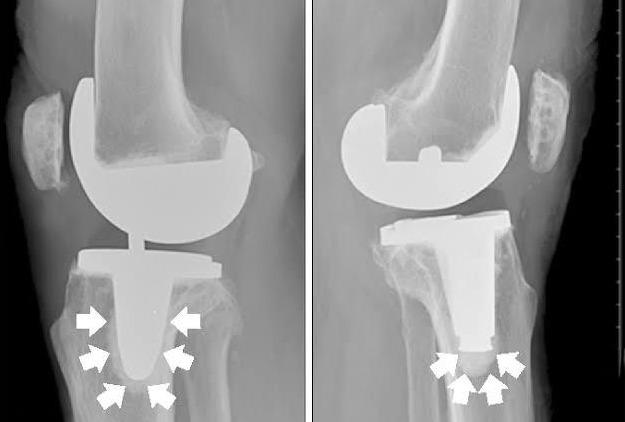

膝关节置换术后,早期康复锻炼至关重要。 一项研究显示,经过平均13个月的随访, 进行早期康复训练的患者优良率可达85.8% 。然而,许多患者因担心疼痛或并发症而不敢积极参与康复。如何克服心理障碍,有效进行康复锻炼,成为术后恢复的关键。

然而, 许多患者因担心疼痛而抗拒锻炼。 一位68岁的患者在术后放松了锻炼,导致膝关节屈曲挛缩,下蹲困难。另一位66岁的患者因严重屈曲挛缩畸形,术后更需注意膝关节伸直情况,加强压腿练习。这些案例说明,克服心理障碍、坚持康复锻炼至关重要。